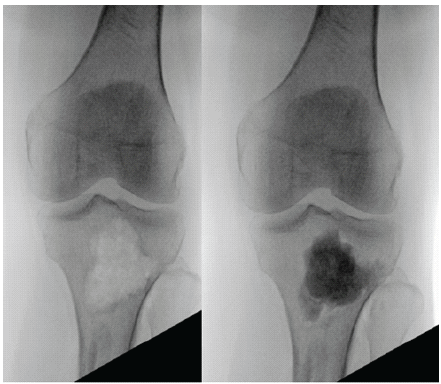

The patient was positioned supine on a flat Jackson table with the operative arm and contralateral leg prepped and draped. We began by harvesting proximal tibial autograft. Under fluoroscopy, a 2 cm incision was centered over the anterolateral aspect of the tibia. Skin and subcutaneous tissues were dissected down to the tibia and an opening cortectomy was made. The AVITUS harvesting suction device was then used under fluoroscopic guidance to retrieved approximately 20 cc of cancellous graft, which was separated from the marrow. The defect was then back filled with 10 cc of tricalcium phosphate bone cement (Fig. 2).

Figure 2: Proximal tibia after graft harvest and after cement backfilling; intraoperative anteroposterior fluoroscopy of the proximal tibia after allograft harvest and after backfilling with bone cement.